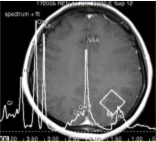

为进一步确诊,MRI增强检查及MRS(Cho升高)结果如下图。可能的诊断为 FSK_MN1_33-2.gif FSK_MN1_33-2-1.gif FSK_MN1_33-2-2.gif

• C.星形细胞瘤

有关星形细胞瘤的MRS,描述正确的是

• B.Cho升高